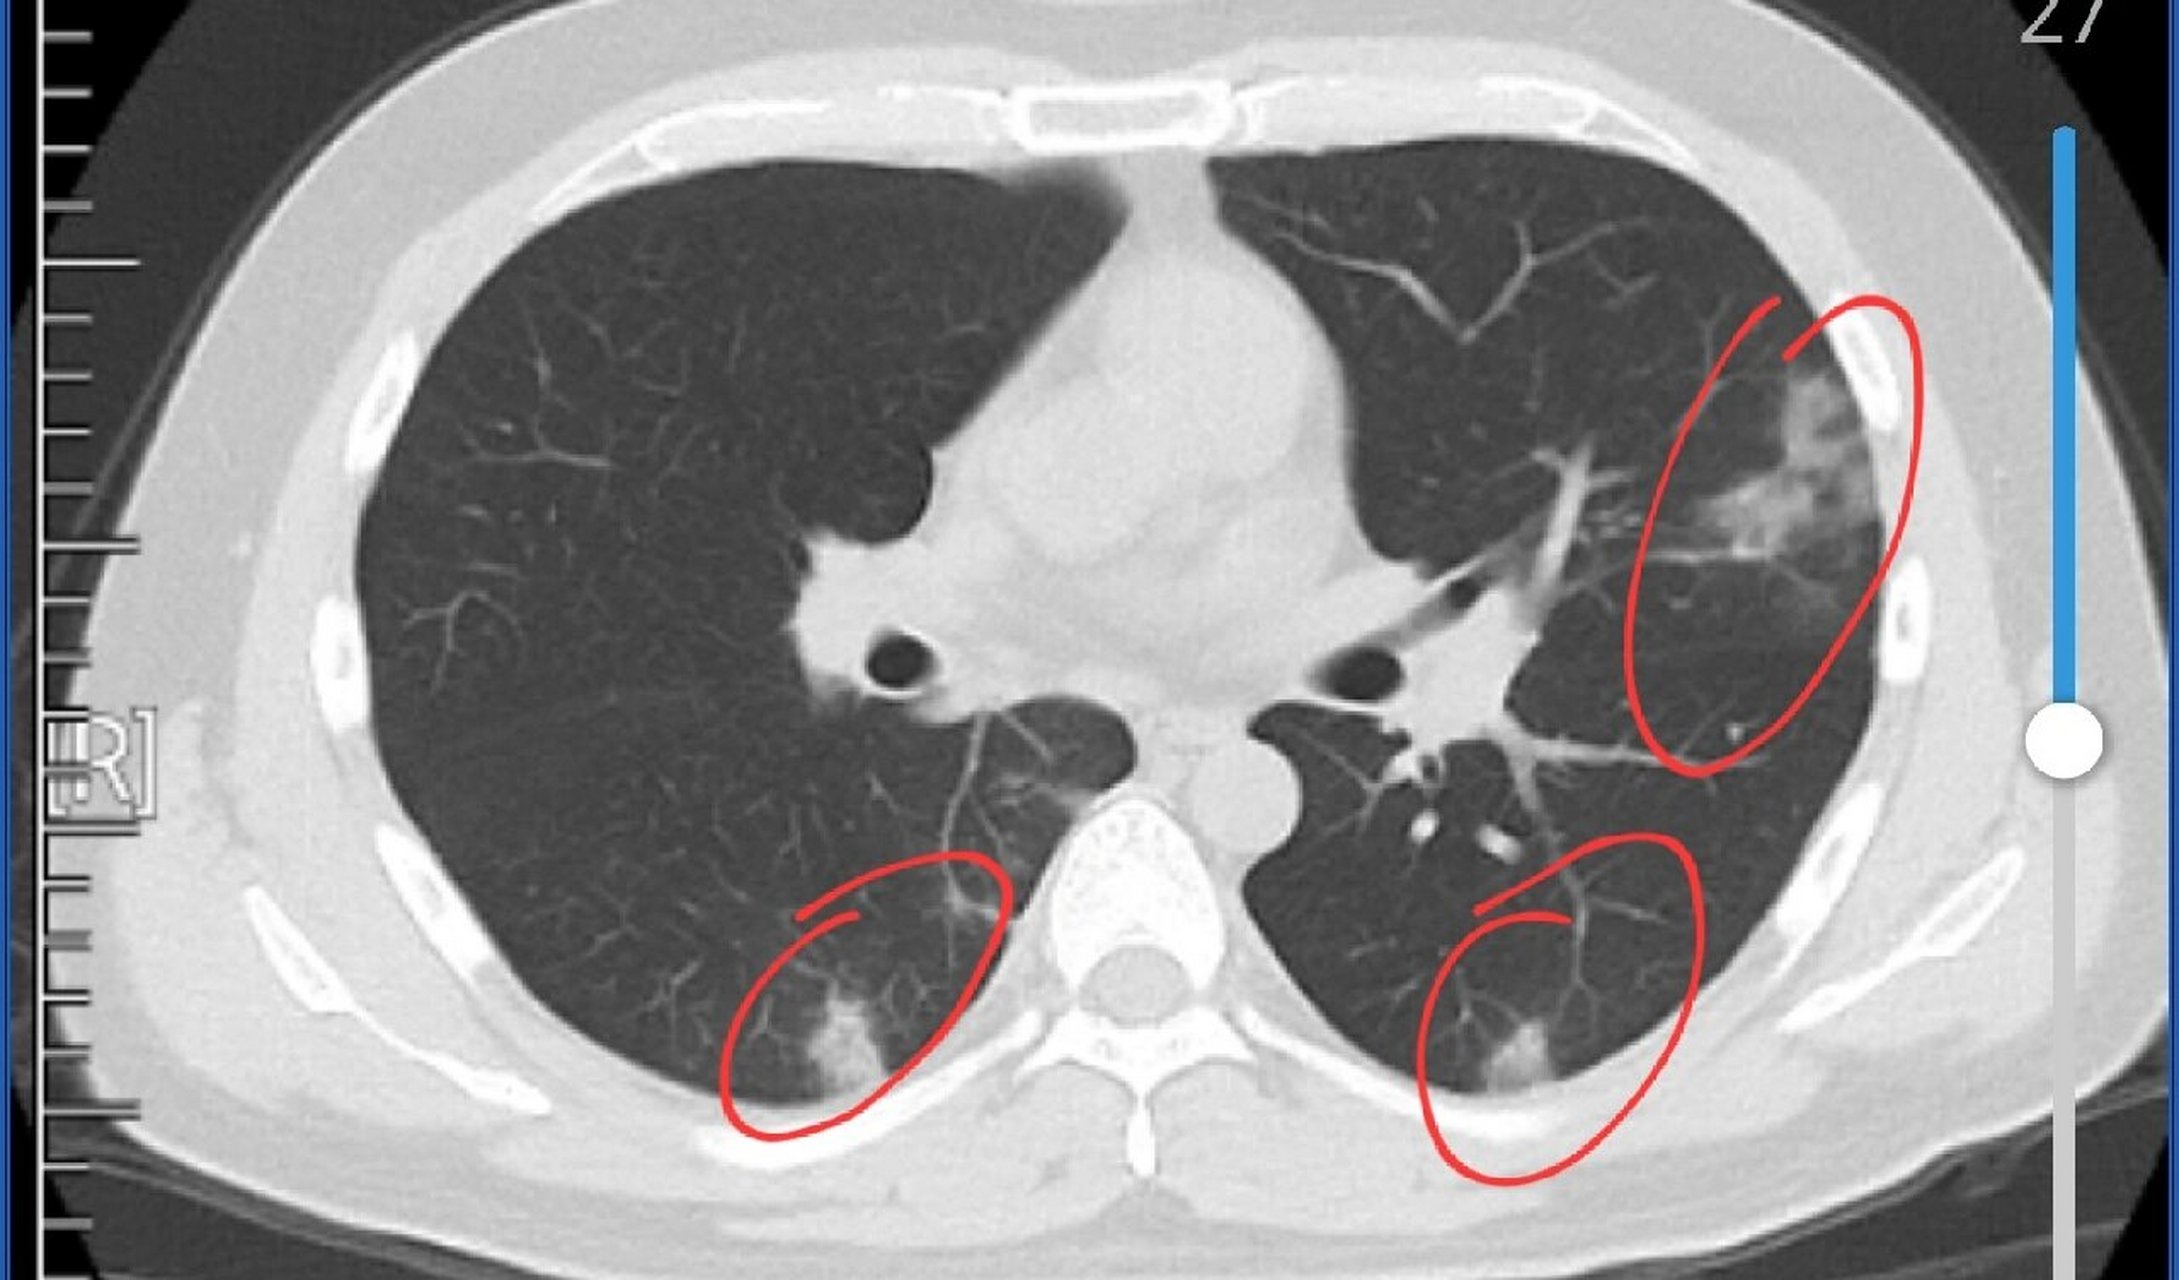

p>新冠肺炎的ct影像学表现 br>新冠肺炎即新型冠状病毒肺炎 br> br>